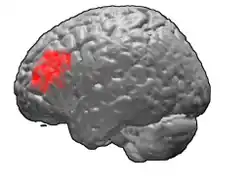

Brodmann area 46, or BA46, is part of the frontal cortex in the human brain. It is between BA10 and BA45.

BA46 is known as middle frontal area 46. In the human brain it occupies approximately the middle third of the middle frontal gyrus and the most rostral portion of the inferior frontal gyrus. Brodmann area 46 roughly corresponds with the dorsolateral prefrontal cortex (DLPFC), although the borders of area 46 are based on cytoarchitecture rather than function. The DLPFC also encompasses part of granular frontal area 9, directly adjacent on the dorsal surface of the cortex.

- Animation.